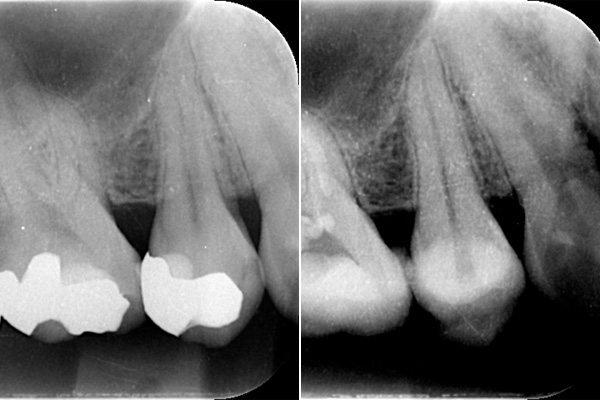

ブリッジが取れたということでご来院患者様でした。レントゲンを撮ると縦に割れていました。

歯を抜くと、やはり割れていました。

歯の破折で抜歯したものです。

断面をみてみえると黒くなっているのがわかります。これは全部細菌です。歯がわれてしまうと、隙間に細菌が住み付き、繁殖してしまいます。そのため、骨や歯茎の中で炎症を起こしてしまいます。破折に気づかず根の治療をしても効果が得られないのです。